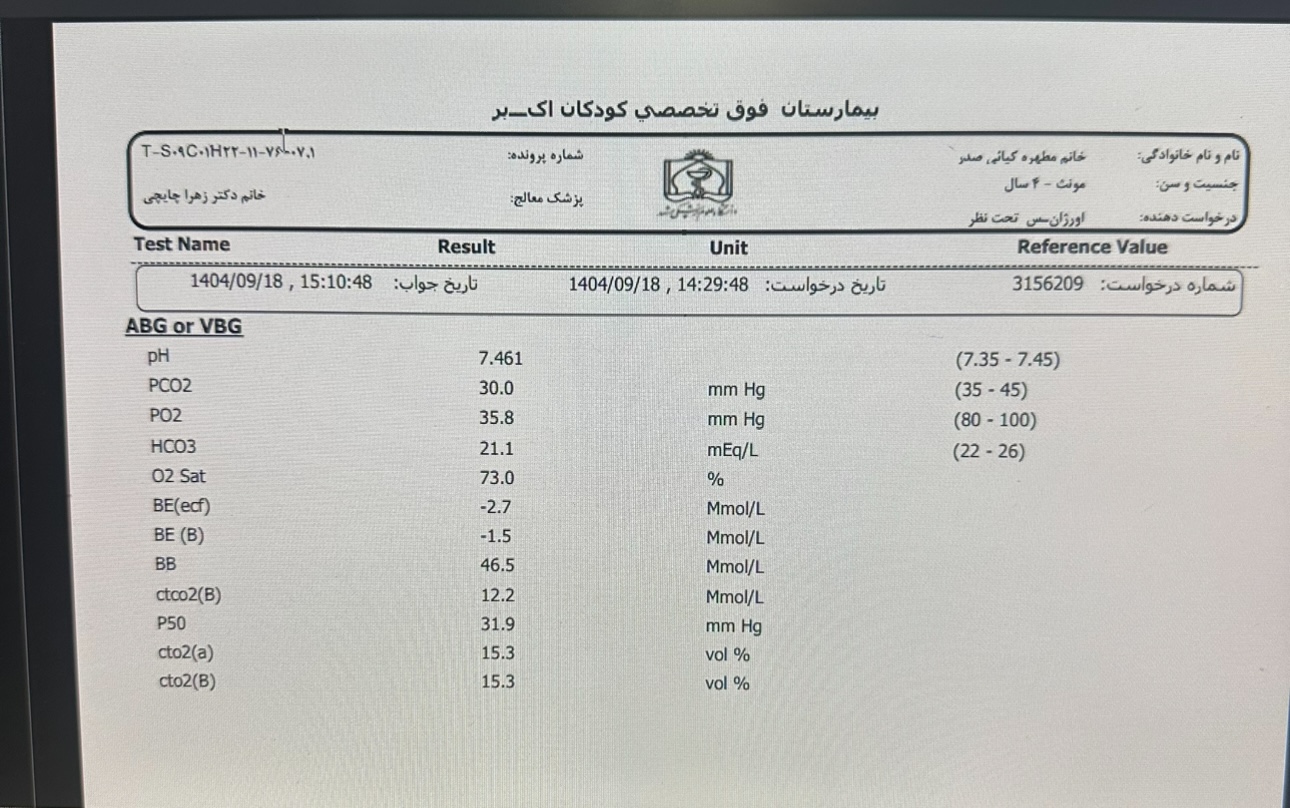

Other:

Other:

Other:

Other: